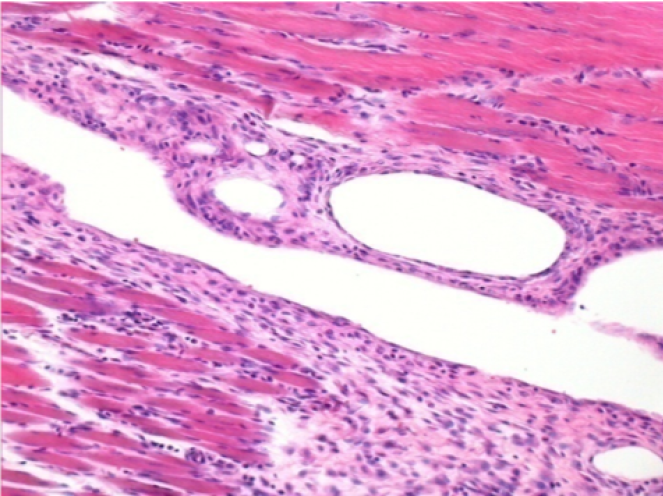

10 giorni dopo iniezione di Endopeel

Scatola Nr 2

- 10 giorni dopo iniezione 0.1ml di Endopeel nel muscolo pretibiale destro (Dx).

- Si osserva formazioni di vacuole , le quali circondate da linfociti.

- Le quali Vacuole sono differenti dal tessuto necrotico.

- La presenza di linfociti é correlata alla permeabilità delle membrane cellulari.

Dx :200x-Giorno10

Dx :400x - Giorno10